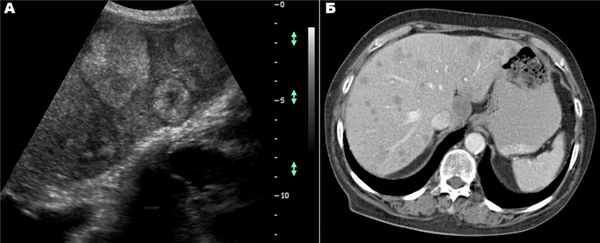

Киста печени

Дифференциальная диагностика ДОП обычно начинается с исключения кист. Чаще встречаются непаразитарные кисты. Учитывается возможность поликистозной болезни, а также солитарных и множественных истинных и ложных кист печени.

Большинство кист небольшие (диаметром 1-5 см), чаще встречаются у женщин. Значительная часть их имеет бессимптомное течение. У ряда больных отмечаются боли в правом подреберье, у одних - постоянные, у других - периодические. Существенную помощь оказывает использование УЗИ и КТ (или ЯМР), обладающие высокой разрешающей способностью. Необходимо учитывать возможность поликистоза печени.

Дифференциальная диагностика простых кист проводится также с паразитарными кистами печени (эхинококкоз). В пользу последних говорят положительные реакции с эхинококковым антигеном и Кацони, а также обнаружение в зоне опухолевидного образования обызвествлений, хотя и геменгиомы изредка могут обызвествлятся.

Важную информацию дают инструментальные исследования. Радионуклидная сцинтиграфия печени выполняется, как обычно, при подозрении на объемный процесс в печени в двух проекциях. Благодаря этому методу, как правило, можно обнаружить опухоль диаметром 4-5 см. При гемангиомах диаметром 4-5 см и более опухоль выявляется у 70-80% обследованных. УЗИ при наличии гемангиомы позволяет выявить гиперэхогенное, хорошо очерченное образование. Подобную же информацию представляет ЯМР. Нередко, особенно в менее массивной левой доле, отчетливо видна сосудистая ножка. Гемангиомы диаметром 3-5 см и более выявляются при УЗИ у 70-80% обследованных. Иногда отмечаются в гемангиомах участки обызвествления.

КТ позволяет получить данные, близкие к результатам УЗИ, хотя нередко приносит и существенную дополнительную диагностическую информацию. Эта дополнительная информация в первую очередь касается состояния окружающих тканей и органов. Целиакография при распознавании гемангиом позволяет получить наиболее точные данные. Обычно хорошо видны гиперваскуляризованные участки с четкими границами, позволяющие обнаружить гемангиому диаметром 2-3 см и более у 80-85% обследованных.